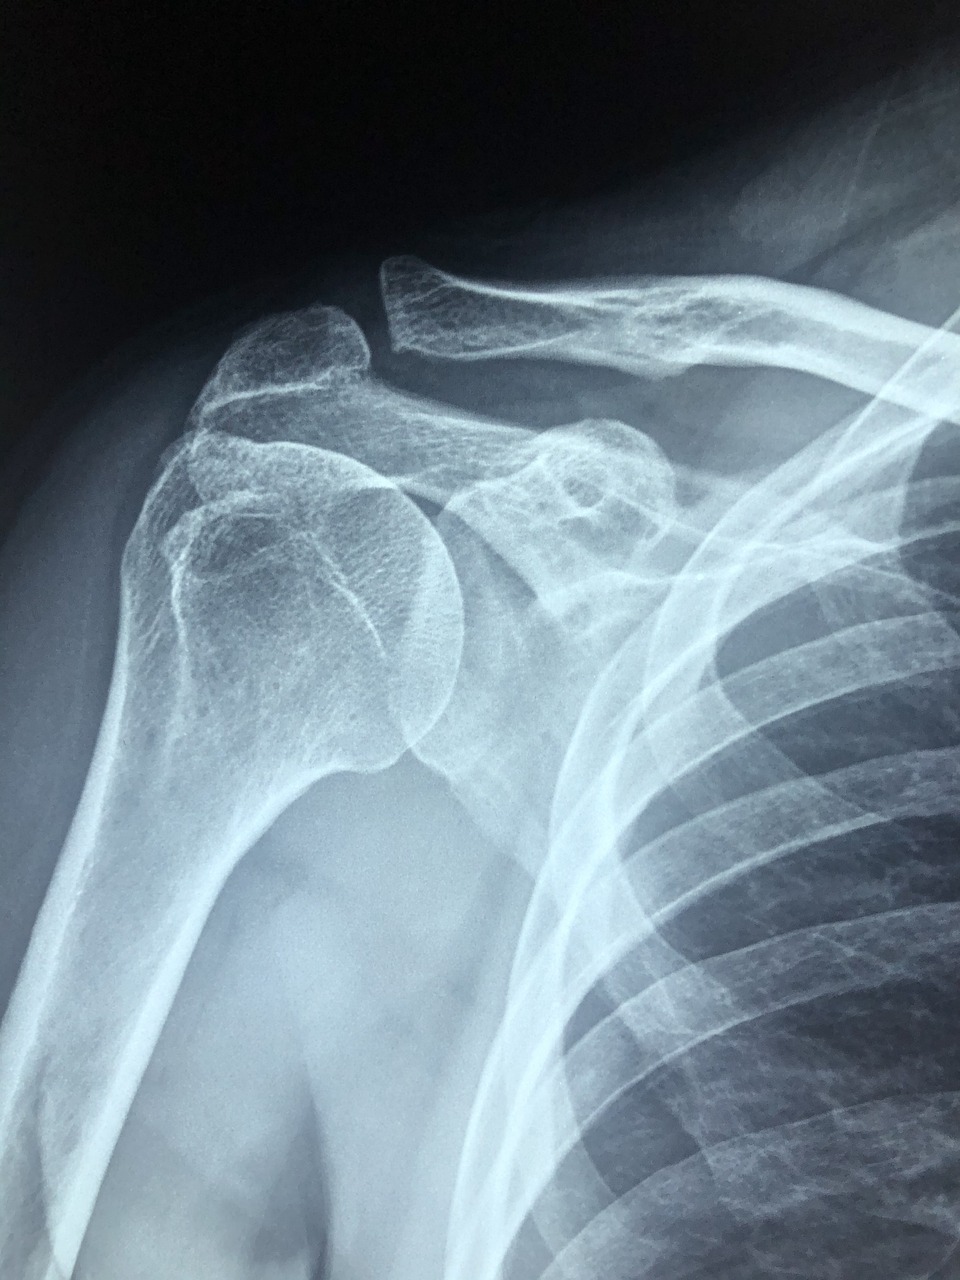

● 어깨석회화건염은 말 그대로 어깨 힘줄 속에 ‘석회질’이 침착되면서 염증을 일으키는 질환입니다.

● 주로 회전근개(어깨를 움직이는 힘줄)에 발생하며, 석회가 자라나면서 힘줄을 자극하고, 이로 인해 극심한 통증을 유발합니다.

💡 갑작스런 통증과 움직임 제한이 있다면 어깨석회화건염을 의심해보세요.

● 조기 발견 시, 비수술적 치료로 충분히 좋아질 수 있으므로 통증이 있다면 빨리 병원에서 정확한 진단을 받는 것이 좋습니다.